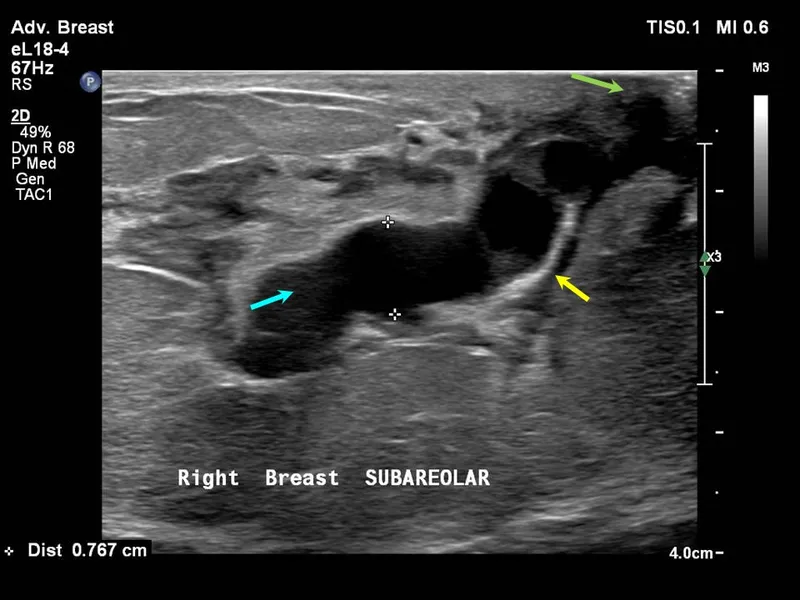

- Duct Ectasia:

- Dilated major subareolar ducts; peri/postmenopausal.

- Nipple discharge (multicolored, sticky), non-cyclical mastalgia, nipple retraction.

- Mammography: Dilated ducts, benign rod-like/secretory calcifications.

- USG: Anechoic/hypoechoic tubular structures, debris, wall thickening.